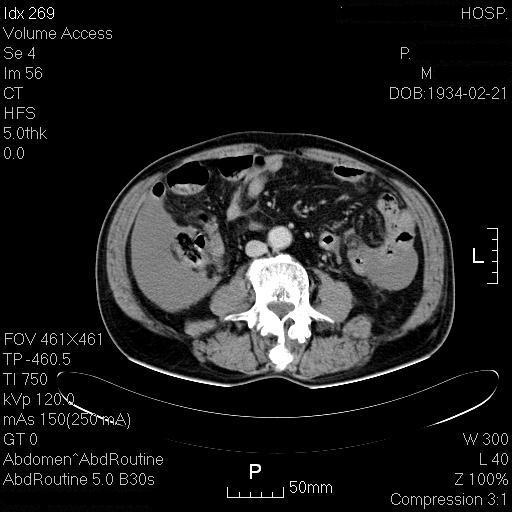

腹腔有积血!!!

肝周有积血!脾脏符合梗塞后改变